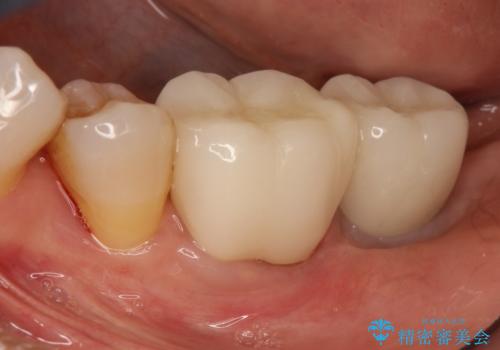

[入れ歯にしたくない] 臼歯部インプラント補綴